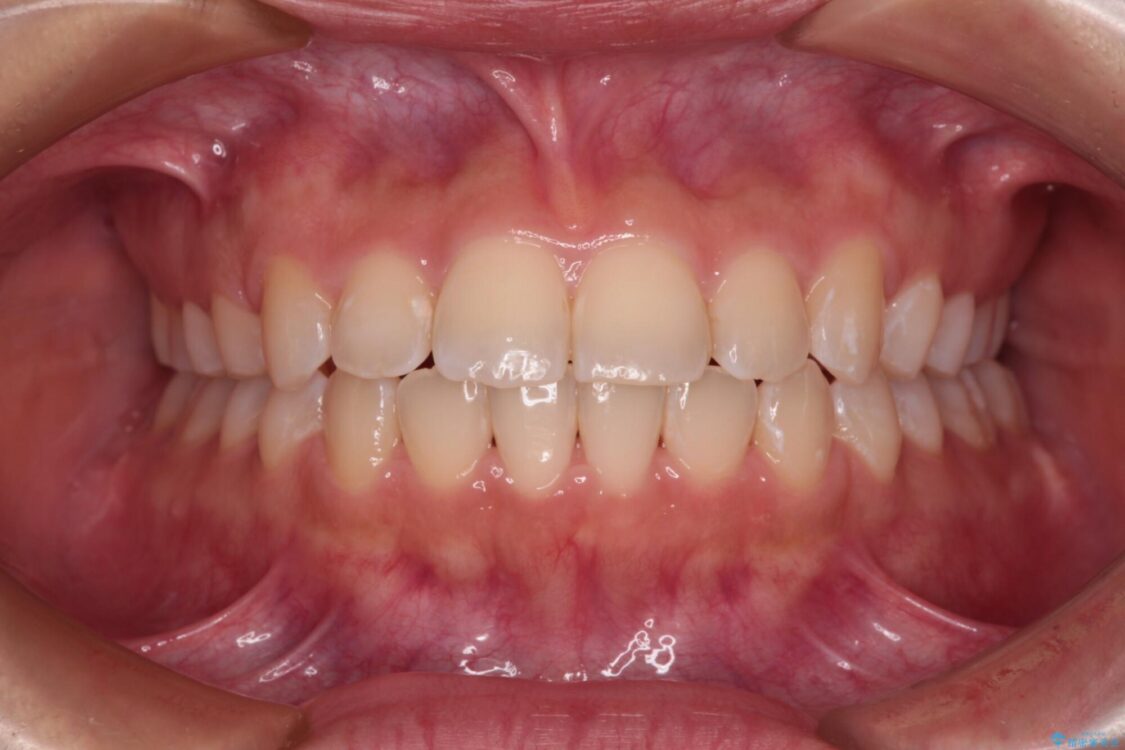

前歯のデコボコを気にして来院された患者様です。

治療後

• 【モニター】短期間で終わりたい ワイヤー装置での非抜歯矯正 治療後画像